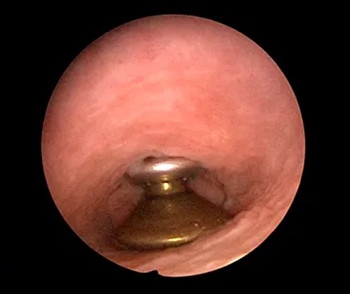

阴道异物竟是一枚硬币

由于异物存在了长达半年时间

(术后询问得知,棉球取出后不久就再次塞入)

硬币与阴道的前后壁及两侧壁

长期压迫和摩擦

发生了粘膜破损

孟主任利用宫腔镜专用异物钳

钳夹住硬币轻轻转动

松动后缓慢平稳的将银币转成斜位

将它慢慢取出

硬币表面锈蚀呈黑褐色